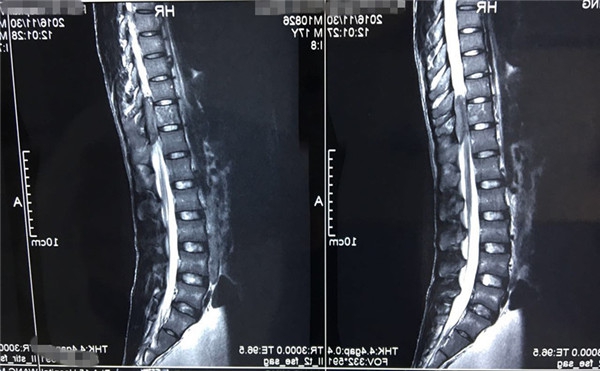

术前MRI

术前 MRI